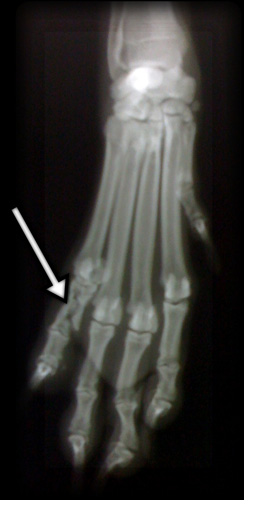

高齢犬・老犬の骨折のほとんどは、交通事故や高いところから飛び降りたり、落下したりして起きます。また病気などで骨がもろくなりおこることもあります。

骨折すると痛みや患部の腫れがおこり、歩行異常などいくつかの症状が同時にあらわれます。

散歩の途中などで飼い主の見ていないすきに、無理をしてしまうケースも考えられます。愛犬が立ち止まり不安な動き、鳴き声をあげるなど普段と違った行動を取った時、飼い主は体全体を優しく触って調べましょう。

歩行が困難だと判断した場合は、足を曲げずに抱きかかえて様子を見ます。痛みなどが激しい場合は、骨折やねん挫などが考えられるので、かかりつけの獣医師に相談しましょう。

皮膚をやぶって骨が飛び出している場合を解放骨折、内部で起きている場合を閉鎖骨折といいます。解放骨折の場合、清潔なガーゼと包帯で保護し、軽い板や新聞紙などを丸めてその上から脱脂綿などを巻いたもので強く締め付けないように固定します。速やかに獣医師に診てもらいましょう。